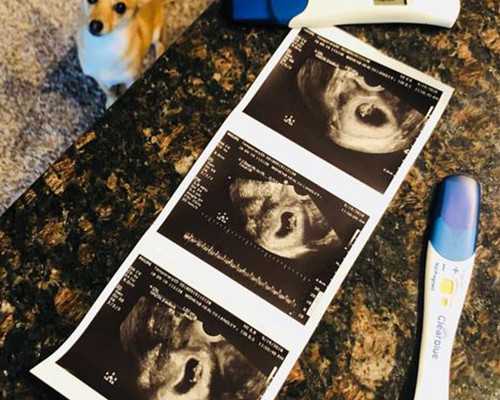

早孕試紙一條杠,是不是沒懷孕?

• 驗孕試紙什么時候能測出懷孕?

• 驗孕試紙準不準?什么時候用最合適

• 驗孕試紙一個月后測準不準

• 驗孕棒怎么用才準?手把手教你正確操作

• 早早孕試紙怎么用?這些細節你得知道

• 早孕試紙怎么用和看結果?簡單幾步教會你

• 早孕試紙去哪買更放心?

• 早孕試紙的正確用法,這些細節你可能不知道